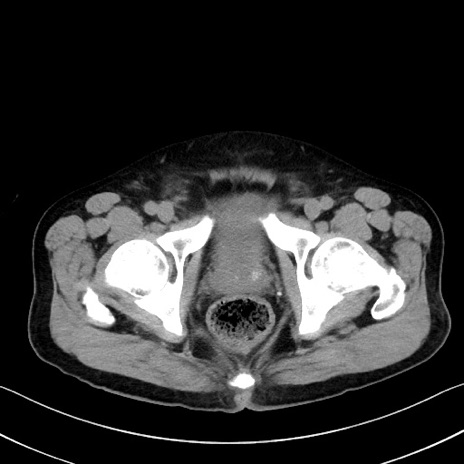

症例35(横断像)

【症例】70歳代 男性

【主訴】腹部膨満、嘔吐

【現病歴】昨日より腹部膨満感出現。本日増悪し、仙痛出現。嘔吐あり、受診。

【既往歴】糖尿病、胆摘後

【身体所見】BP 149/80mmHg、HR 74/min、BT 35.9℃、腹部:膨満、軟、圧痛なし。腸雑音減弱あり。上腹部正中切開瘢痕あり。

【データ】WBC 13500、CRP 1.72